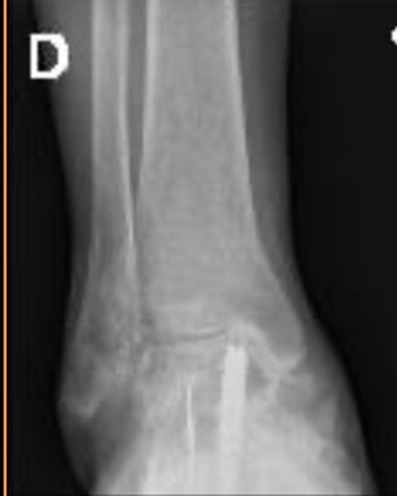

Este procedimiento quirúrgico consiste en sustituir la articulación dañada por una prótesis compuesta de metal y plástico, diseñada para restaurar la movilidad y aliviar el dolor.